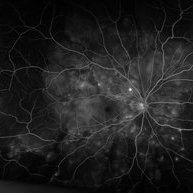

"Starry Sky" Fundus in Vogt-Koyanaki-Harada Syndrome

Jan 10 2018 by Peter H. Tang, MD, PhD

Fluorescein angiography imaging of a 27-year-old male with acute inflammation as part of Vogt-Koyanagi-Harada Syndrome.

Imaging device: Optos California